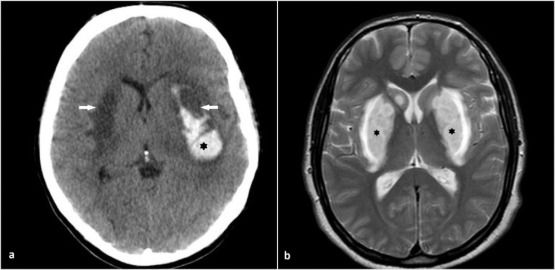

Case History: 67-year-old female presented with one week of vision problems.